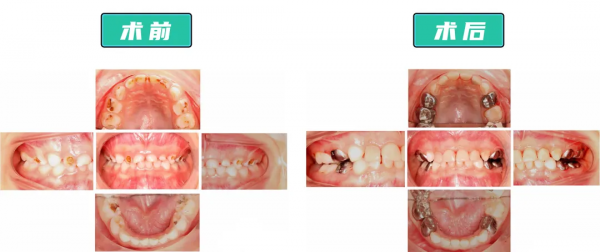

醫生給童童沒那麼嚴重的前牙“套上”了透明樹脂預成冠,針對要受力咀嚼、不太影響美觀的後牙,“套上”了相對不易磨損脫落、可承受壓力更大、價效比更高的金屬預成冠。

整個過程治療了17顆齲齒,做了12顆預成冠,一次性解決了童童的口腔問題。